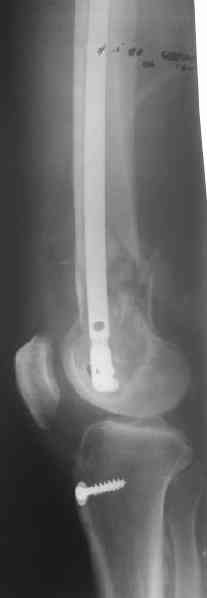

Длину восстановили, возможно, даже с изьбытком, ну да динамизируем пораньше. Введенные в овальное отверстие дистальые винты имеют угловую стабильность. Снимки приложены. Заранее спасибо за критику и комментарии.

Довольно симпатично получилось. Не сомневался, что будет именно такой антеградный реостеосинтез.

Была ли педресация на столе после окончательной фиксации? Уверен ли ты, что "угловая стабильность" дистальных винтов позволит агрессивно заниматься разработкой движений в коленном суставе?

Nicely executed surgery with good planning resulting in great looking x-rays but not the best the way to deal with this fracture. Earlier fracture was having slight translation with no angulation and no instability, now ur fracture is distracted with potential instability as your construct is not the best suited to this place, so more likelihood of non union or complications.

Good luck to you and your patient

Should have preferred a locking plate if at all u wanted to reoperate and

added copious bone graft.